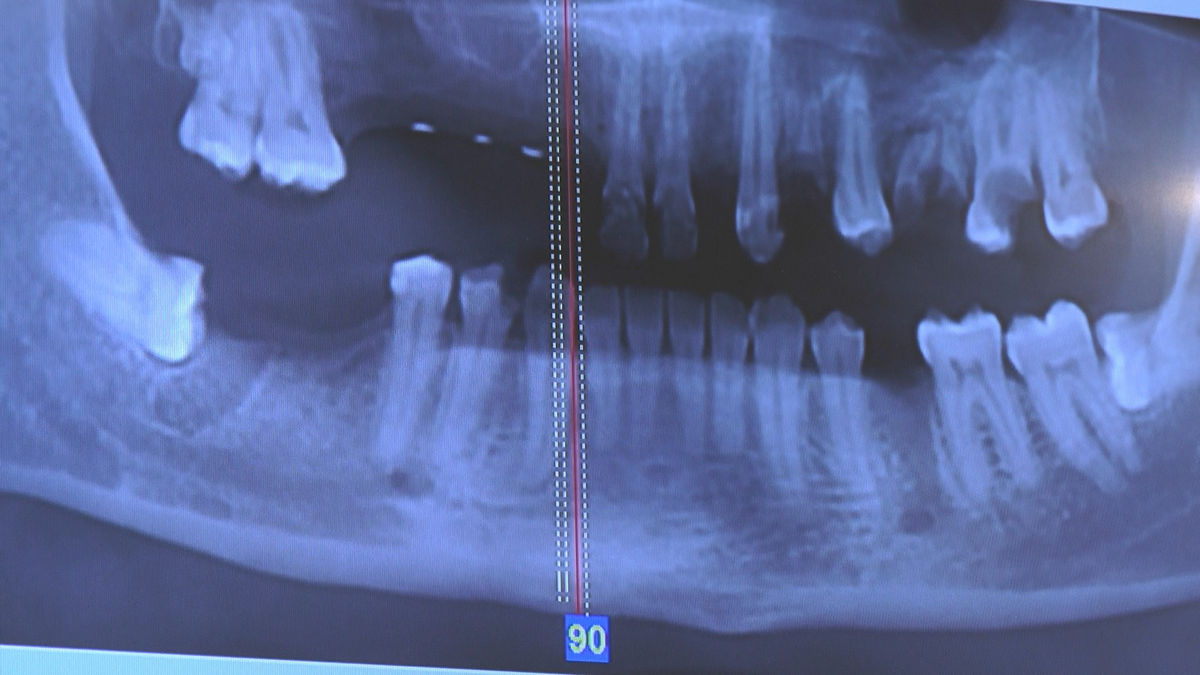

Tuż przed 100 Rocznicą Odzyskania Niepodległości, 9 i 10 listopada 2018 roku, kursanci VI Sezonu Practiculum Implantologii odbyli 7 Sesję. Dwa dni intensywnego szkolenia poświęcone zostały na zabiegi z zakresu chirurgii implantologicznej. Kursanci wykonali szereg zabiegów u Pacjentów pod kierunkiem Mentorów – dr n.med. Violetty Szycik i dr n.med. Magdaleny Kisłowskiej-Syryczyńskiej. Jak zwykle nie zaliczały się one do najłatwiejszych. W większości były przeprowadzone w arcytrudnych warunkach wynikających przede wszystkim ze stanu tkanki kostnej oraz stanu zdrowia, co wymagało precyzyjnego planowania. Z zabiegów skorzystało 17 Pacjentów, także z zastosowaniem znieczulenia ogólnego w formie sedacji dożylnej. Wszczepiono 23 implanty, wykonano zabiegi natychmiastowej implantacji po mnogich ekstrakcjach, przeprowadzono zabiegi augmentacji oraz 3 zabiegi sinus lift z zastosowaniem preparatów kościozastępczych i PRF. Wszystkie zabiegi przeprowadzane zostały zgodnie z planem i dużym stopniem samodzielności, który odpowiada zakresowi poszerzających się umiejętności szkolących się lekarzy. W panelu edukacyjnym Sukces Twojego Biznesu odbyły się pierwsze zajęcia z NLP. Kolejna 8 sesja już na początku grudnia.